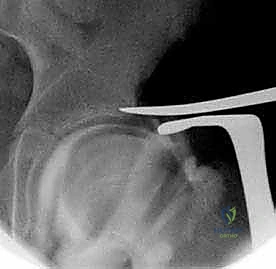

3. تقييم الشفا الحُقي (Labrum Assessment)

بمجرد فتح الكبسولة، يتم فحص الشفا الحُقي بصرياً. إذا كان الشفا منقلباً للداخل أو ممزقاً بسبب الانزلاق المحوري، يتم تحريره وإعادته إلى وضعه التشريحي الصحيح.

5. بناء الرفرف (Creating the Shelf)

هنا تتجلى مهارة الأستاذ الدكتور محمد هطيف؛ حيث يقوم بإحداث شق دقيق فوق حافة التجويف الحُقي، ويدرج الطُعم العظمي بقوة داخل هذا الشق. يتم توجيه الطُعم بحيث يمتد للخارج وللأسفل، مشكلاً سقفاً صلباً يغطي رأس الفخذ البارز.